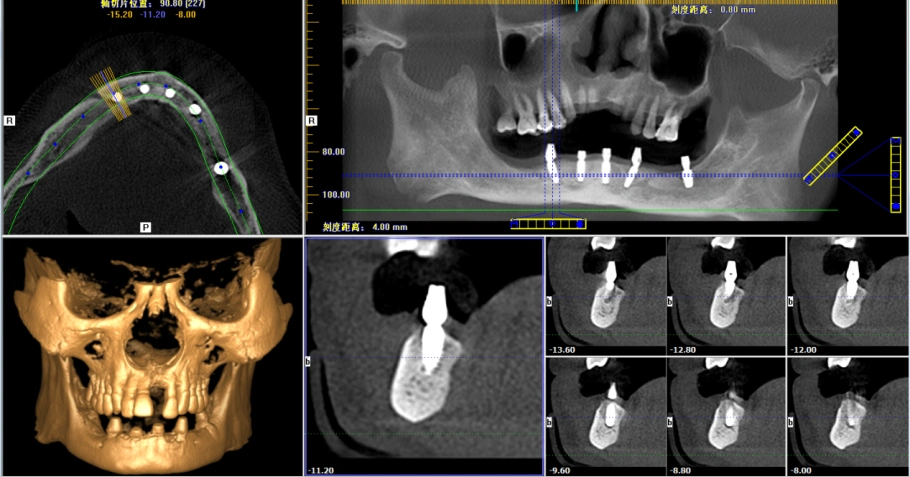

种植体植入后的cbct